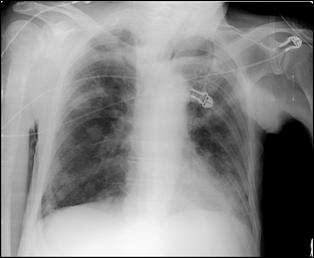

Cele mai multe metasteze la distanta, provocate de tumorile vezicale maligne, sunt localizate in plamani si in oase. Diagnosticul acestora se face prin: radiografii toraco-pulmonare, radiografii osoase sau scintigrame osoase (evidentiaza metastazele osoase cu 9-12 luni mai devreme decat expresia evidenta a acestora pe radiografiile standard).

dreapta Figura 45. Metastaze pulmonare multiple dintr-un carcinom vezical

infiltrativ.

Figura 4 Radiografie toraco-pulmonara cu metastaze pulmonare multiple

dintr-un carcinom vezical infiltrativ

Figura 47. Radiografie toraco-pulmonara cu metastaze pulmonare multiple dintr-un carcinom vezical infiltrativ.